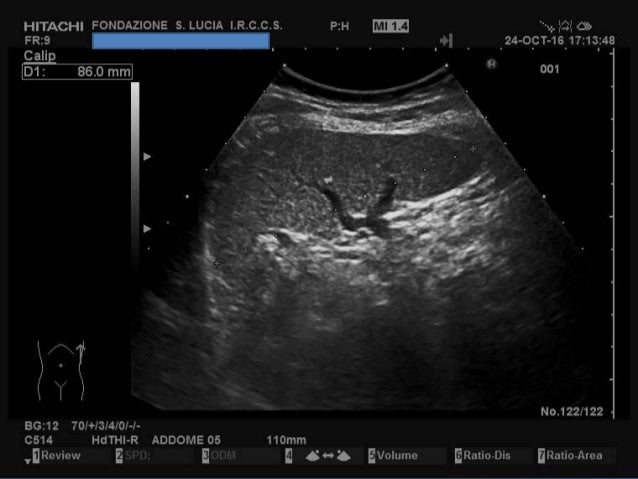

La milza ha la forma di un ovoide appiattito, con il maggior asse orientato obliquamente, dall’alto in basso, da dietro in avanti e dall’interno all’esterno;. La milza è un organo interno, delle dimensioni di un pugno, che si trova nell'addome umano Le funzioni della milza come parte del sistema immunitario e contribuisce alla produzione e stoccaggio di globuli come parte del sistema circolatorio Anche se la milza è un organo importante, ma non è essenziale per la sopravvivenza umana. Ecografia dell'addome superiore tecnica di misurazione delle dimensioni della milza normale, nel caso in esame.

Le dimensioni di una milza normale e sana possono variare considerevolmente da persona a persona Anche il tuo sesso e la tua altezza possono influenzare le sue dimensioni In generale, una milza adulta è lunga circa 5 pollici, larga 3 pollici, spessa 1,5 pollici e pesa circa 6 once. Ecografia dell'addome superiore tecnica di misurazione delle dimensioni della milza normale, nel caso in esame. Oltre alle dimensioni della milza, altri parametri devono essere presi in considerazione per la valutazione dei rischi connessi alla procedura Infatti, il tipo di patologia ematologica può giocare un ruolo fondamentale Inoltre, altri parametri relativi allo spazio di lavoro addominale sono da considerare, come l'habitus corporeo, l'indice di.

Fra le più importanti si ricordano quella emocateretica (distruzione dei globuli rossi non funzionali o deteriorati), quella immunologica, quella emopoietica e quella di separazione delle cellule ematiche e del plasma. Ecografia dell'addome superiore tecnica di misurazione delle dimensioni della milza normale, nel caso in esame. Pesa da 180 a 250 g ma questo valore, insieme alle dimensioni, varia in funzione della quantità di sangue che l.